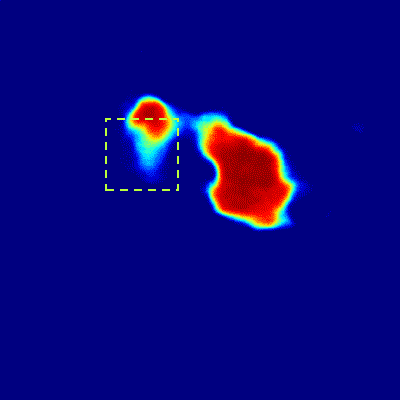

From above, the CNN sub-network processes pancreas segmentation on individual 2D image slices, delivering remarkable performance on the tested CT and MRI datasets. However, as shown in the first row of Fig. 4, the transition among the resulted CNN pancreas segmentation regions in consecutive slices may not be smooth, often implying that segmentation failure occurs. Adjacent CT/MRI slices are expected to be correlated to each other thus segmentation results from successive slices need to be constrained for shape continuity and regularization. The model for 3D object segmentation is required to be able to detect and recover abnormally lost part inside slices (see Y^τsubscript^𝑌𝜏\hat{Y}_{\tau} in Fig .4).

Figure 4: The main construction units of the proposed RNN sub-network and its input/output segmentation sequence. The sequence of CNN sub-network outputs is shown in the first row (a-e), is taken as the input of the bi-direction CLSTM (g), which is an RNN architecture composed of 2 layers of CLSTM (f) working in opposite directions. The third row (h-l) presents the corresponding output sequence, which is sharp and clean. Note that the missing pancreatic part in Y^τsubscript^𝑌𝜏\hat{Y}_{\tau} (c), in the green dashed box, is recovered by shape continuity modeling in Y¯τsubscript¯𝑌𝜏\bar{Y}_{\tau} (j). For visual clearity, we ommit the input Y^()subscript^𝑌\hat{Y}_{(\cdot)} in the bi-direction CLSTM (g), which is same as in (f).